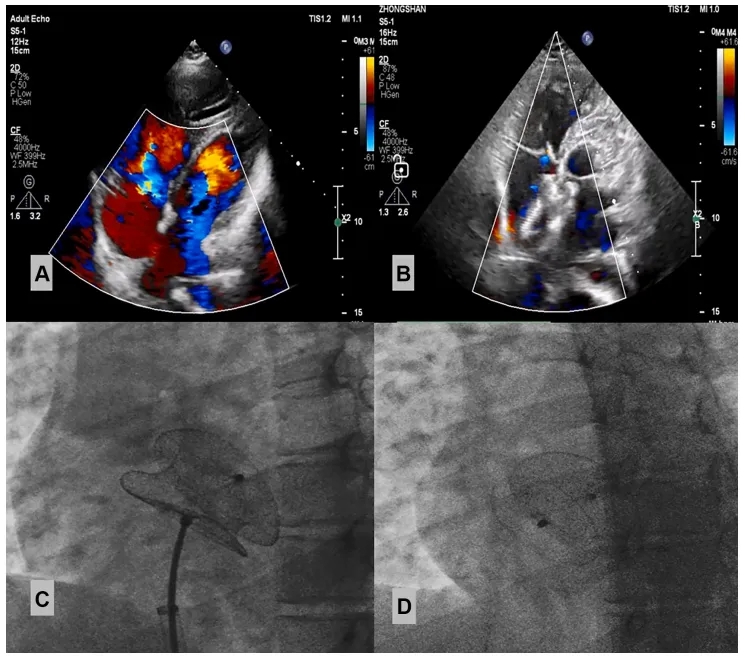

2025年3月17日:两个月后患者接受经皮ASD封堵术,右心导管检查示PAP 62/23(40)mmHg,Qp/Qs为2.5,PVR 3.41 WU。术中选择32mmASD封堵器成功实施封堵,术后PAP 51/20(32)mmHg,超声心动图提示封堵器位置、大小及形状合适,未影响周边心脏结构(图2)。

图2:经皮ASD封堵术前后超声心动图

(A)术前超声心动图显示ASD,(B)封堵完成后超声心动图,(C)术中封堵,(D)释放封堵器后。